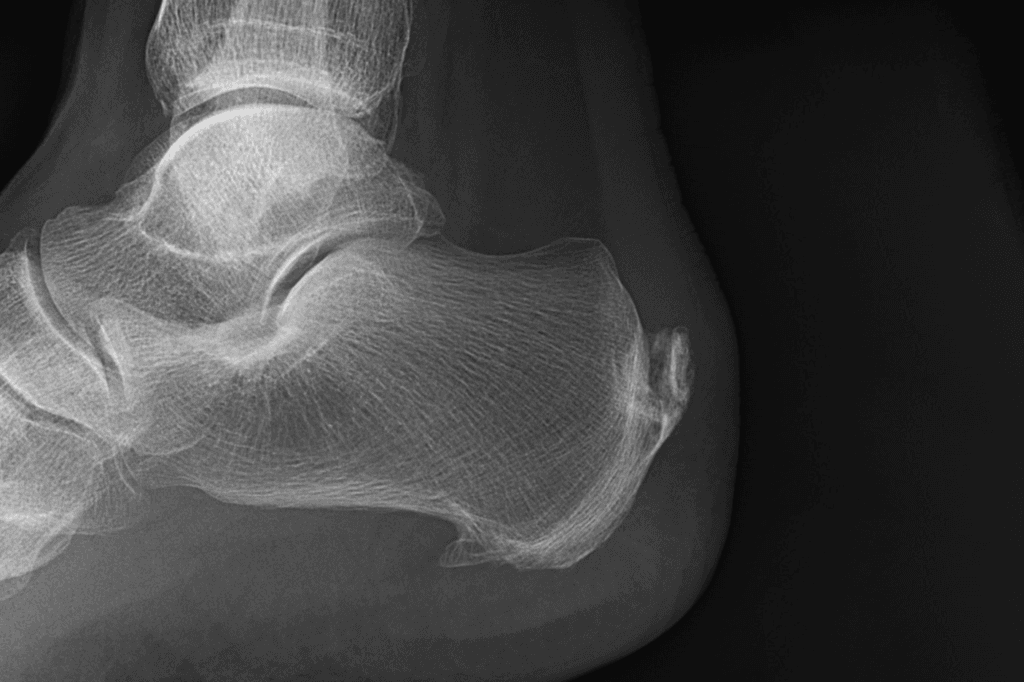

Esporão de Calcâneo e Fascite Plantar

O Prof. Frederico Meirelles fala sobre o Mito do Esporão de Calcâneo e explica a Fascite Plantar. Essas condições são muito comuns nos atendimentos.